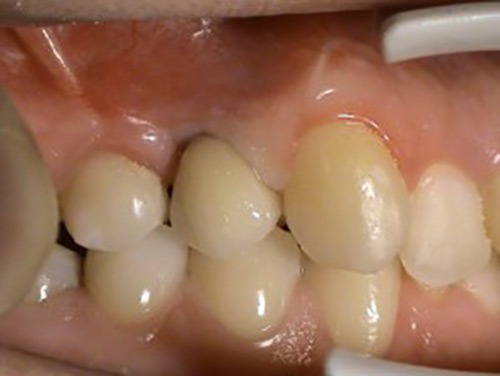

1. PHASE – implant insertion